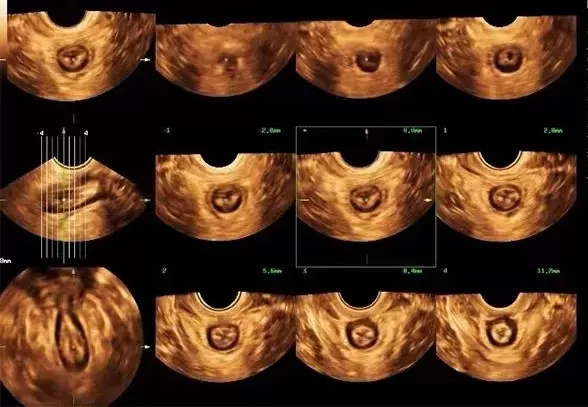

自贡市第一人民医院超声医学科主任吴萍介绍到,对于盆底功能障碍性疾病,最常见的一种检查方式就是盆底超声。这种检查具有无辐射、无创伤、可重复性好、实时动态、价格低廉等优势,有利于疾病的早期发现、早期诊断等优点。盆底超声通过利用超声探头经会阴、阴道或直肠检查,观察在静息、缩肛及Valsalva(乏氏动作,也就是我们常说的吸气、憋气)三种状态下的盆腔脏器位置变化,结合二维、三维、四维多种成像方法评估盆腔脏器脱垂程度、肛提肌裂孔大小及肛提肌、肛门内外括约肌的完整性,同时能评估尿道、阴道及肛门周围病变,也能用于盆底修复术前、术后及盆底康复疗效的评估。

d1.webp 断层超声成像模式评估肛提肌及肛门括约肌连续性像妊娠及分娩后盆底功能评估、排尿异常,压力性尿失禁、排尿困难、排便障碍,大便失禁、便秘、阴道前壁、阴道后壁膨出、子宫脱垂、肛提肌和肛门括约肌等盆底肌损伤等患者都可以适用盆底超声进行检查。